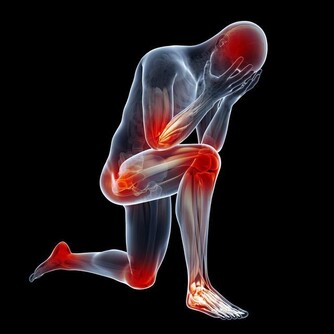

2、各種骨骼疾病

鈣缺乏很容易導致骨骼疾病和兒童。如果缺鈣會導致佝僂病,雞胸,缺鈣的孩子會出現生長痛,如果成人缺鈣會導致腰酸背痛、骨質增生。退行性病變,老年人缺鈣就會導致骨質疏鬆,容易骨折。很多老年人因為缺鈣,50以上就會出現駝背,還有一些人因為缺鈣,導致股骨頭壞死。

3、女性痛經

人的疼痛的感覺是由神經傳導和控制,如果缺鈣,女性就會表現為非常明顯的痛經,因為缺少鈣,導致神經敏感,痛感更強。所以,如果患有經前期綜合徵的女性朋友如果平時注意多補充一些優質的鈣,是非常有必要的。